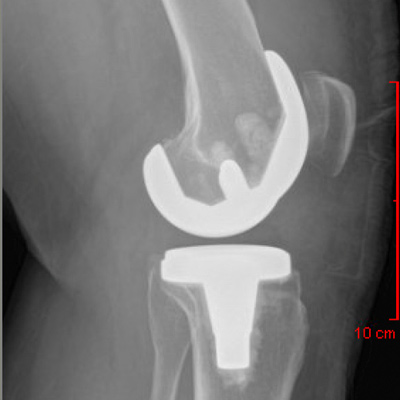

Anterior-Posterior View Total Knee Replacement